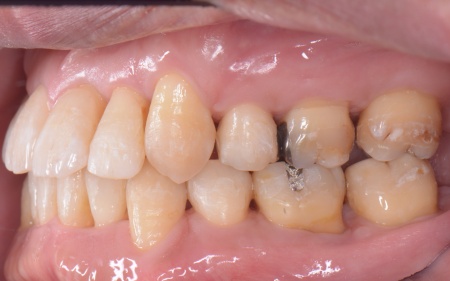

拝見したところ、上下の歯は、ずれたりねじれたりしてデコボコに生えており、著しく歯並びが乱れていました。

さらに、左下奥歯は重度の歯周病であり、歯を支えている骨が一部溶けていることが判明しました。

②矯正治療後、歯周病を発症している左下奥歯(第1大臼歯)を温存するために、失われた骨や歯茎を再生する「歯周再生療法」を行う

その後、左下奥歯に歯周再生療法を行って歯周病が改善したことを確認し、治療を終了しました。